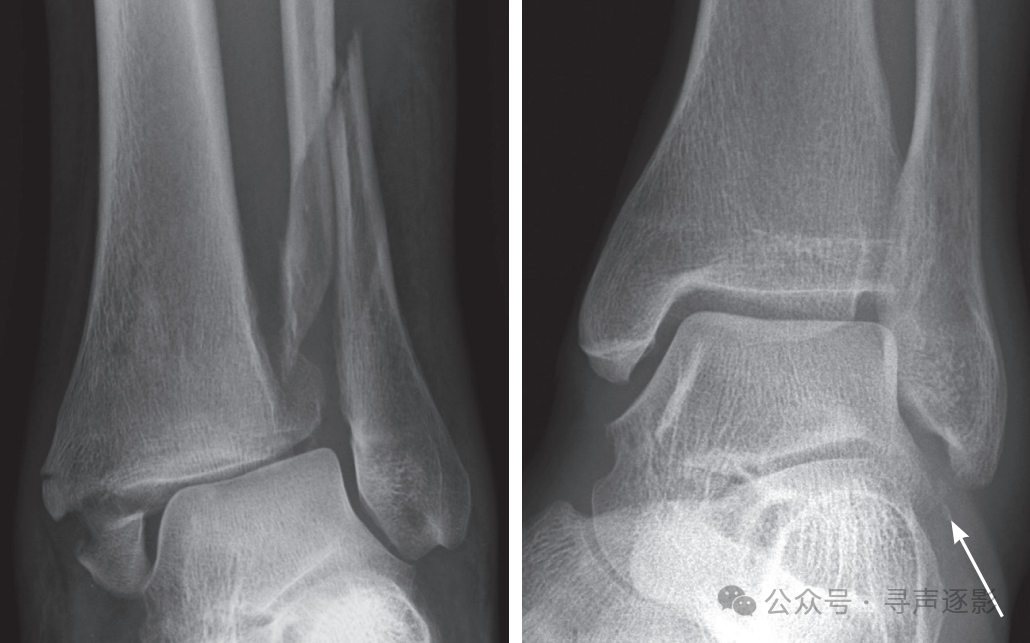

左图:距骨颈骨折,移位(箭头)。右图:距骨颈骨折,无移位(箭头)。

🚩距骨颈骨折:易缺血坏死

• 移位越明显 → 缺血坏死(AVN)概率越高

• 无移位骨折 X 线“细如发丝”,最容易被忽略

• 结局:一旦坏死,后期关节炎跑不掉